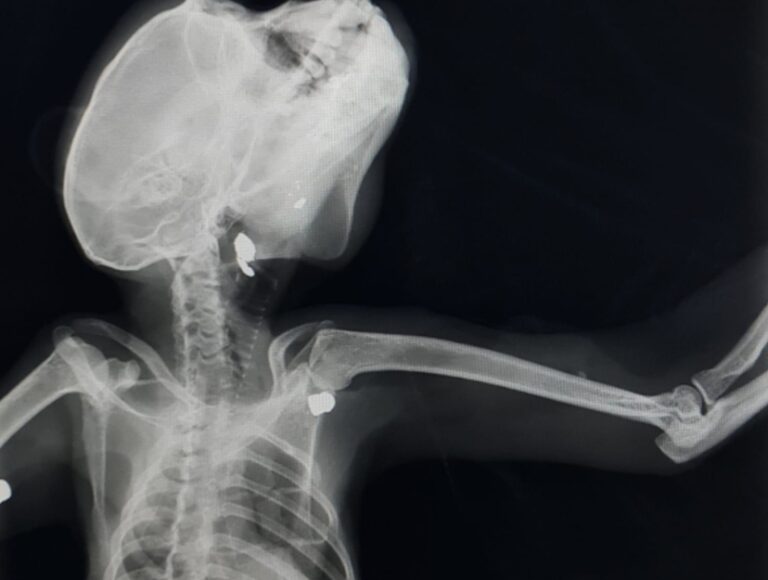

Macaco com fratura exposta